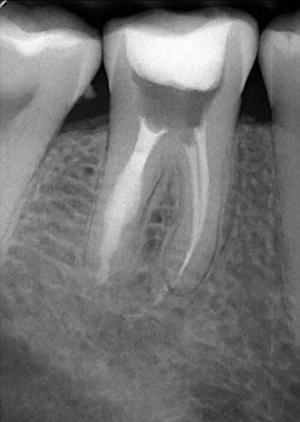

牙內(nèi)吸收通常無(wú)明顯癥狀。根據(jù)吸收的類型和原因,主要分為炎癥性吸收和替代性吸收。其中,炎癥性吸收可能繼發(fā)于前期牙本質(zhì)的細(xì)菌感染和創(chuàng)傷,牙本質(zhì)吸收過(guò)程的進(jìn)展不伴有吸收區(qū)鄰近部位硬組織的沉積,吸收部位可見(jiàn)大量肉芽組織,典型的影像學(xué)表現(xiàn)為,以根管為中心的橢圓形透光區(qū)。替代性吸收,導(dǎo)致根管內(nèi)牙本質(zhì)缺損的同時(shí),在缺損區(qū)某些部位還伴有骨樣組織的沉積,造成牙髓腔不規(guī)則的擴(kuò)大和根管連續(xù)性的破壞。根據(jù)牙內(nèi)吸收發(fā)生部位和嚴(yán)重程度的不同,又可呈現(xiàn)不同的征象。若吸收部位發(fā)展至牙冠,可以觀察到牙冠上出現(xiàn)粉紅色的點(diǎn),這是吸收細(xì)胞鄰近的結(jié)締組織高度血管化的結(jié)果。當(dāng)吸收部位位于根方,則可使得根管原有的形態(tài)缺失,X線片可見(jiàn)根管局部氣球樣的膨大,通常邊界清晰。若牙髓還有部分的活力,則患牙可能有慢性牙髓炎的表現(xiàn);若牙髓完全壞死,則可能發(fā)展成根尖周炎,而出現(xiàn)相應(yīng)的癥狀。竇道的出現(xiàn)往往是己發(fā)生慢性根尖膿腫或根管側(cè)穿的表現(xiàn)。由于患牙冠方的牙髓通常己經(jīng)壞死或被去除,因此敏感性測(cè)試常為陰性。

3.牙內(nèi)吸收的治療

牙內(nèi)吸收一旦確診,則需要對(duì)患牙的預(yù)后做出判斷。對(duì)于有保留價(jià)值的患牙,應(yīng)該及時(shí)行根管治療。對(duì)于未發(fā)生根管側(cè)穿者,應(yīng)完全去除根管內(nèi)吸收組織,以防止其牙體硬組織的進(jìn)一步破壞。牙內(nèi)吸收所導(dǎo)致的病損的特點(diǎn),給根管治療帶來(lái)了難度。行根管預(yù)備時(shí),應(yīng)盡量保守,以最大程度的保留牙體組織,以免對(duì)本就薄弱的根管壁造成進(jìn)一步的損害。對(duì)于有活動(dòng)性吸收的患牙,在治療過(guò)程中,炎癥牙髓和肉芽組織可能出現(xiàn)大量的滲血從而影響操作視野。同時(shí),機(jī)械預(yù)備的方法往往不能完全達(dá)到吸收所造成的缺損部位。因此,根管預(yù)備時(shí)次氯酸鈉和超聲設(shè)備的作用就顯得尤為重要。次氯酸鈉可以溶解壞死的牙髓組織。超聲的震蕩可以使次氯酸鈉沖洗液活化,并充分滲透到根管系統(tǒng)的每個(gè)角落,以減少根管內(nèi)細(xì)菌的數(shù)量。然而,即使使用了超聲設(shè)備,往往根管內(nèi)局部還是會(huì)有細(xì)菌的殘留因此,根管內(nèi)封藥應(yīng)該具有良好的抗菌作用,以提高器械所不能到達(dá)部位的消毒。氫氧化鈣糊劑對(duì)根管內(nèi)多種細(xì)菌有殺傷作用,并可滲入牙本質(zhì)小管發(fā)揮殺菌作用,效果明顯。此外有研究證實(shí),氫氧化鈣與次氯酸鈉有協(xié)同作用,可減少根管內(nèi)有機(jī)碎屑的殘留囚。對(duì)于根管的充填,應(yīng)選擇具有良好流動(dòng)性的充填材料,來(lái)封閉吸收所造成的缺損。其中,熱塑性牙膠充填技術(shù)最為常用。